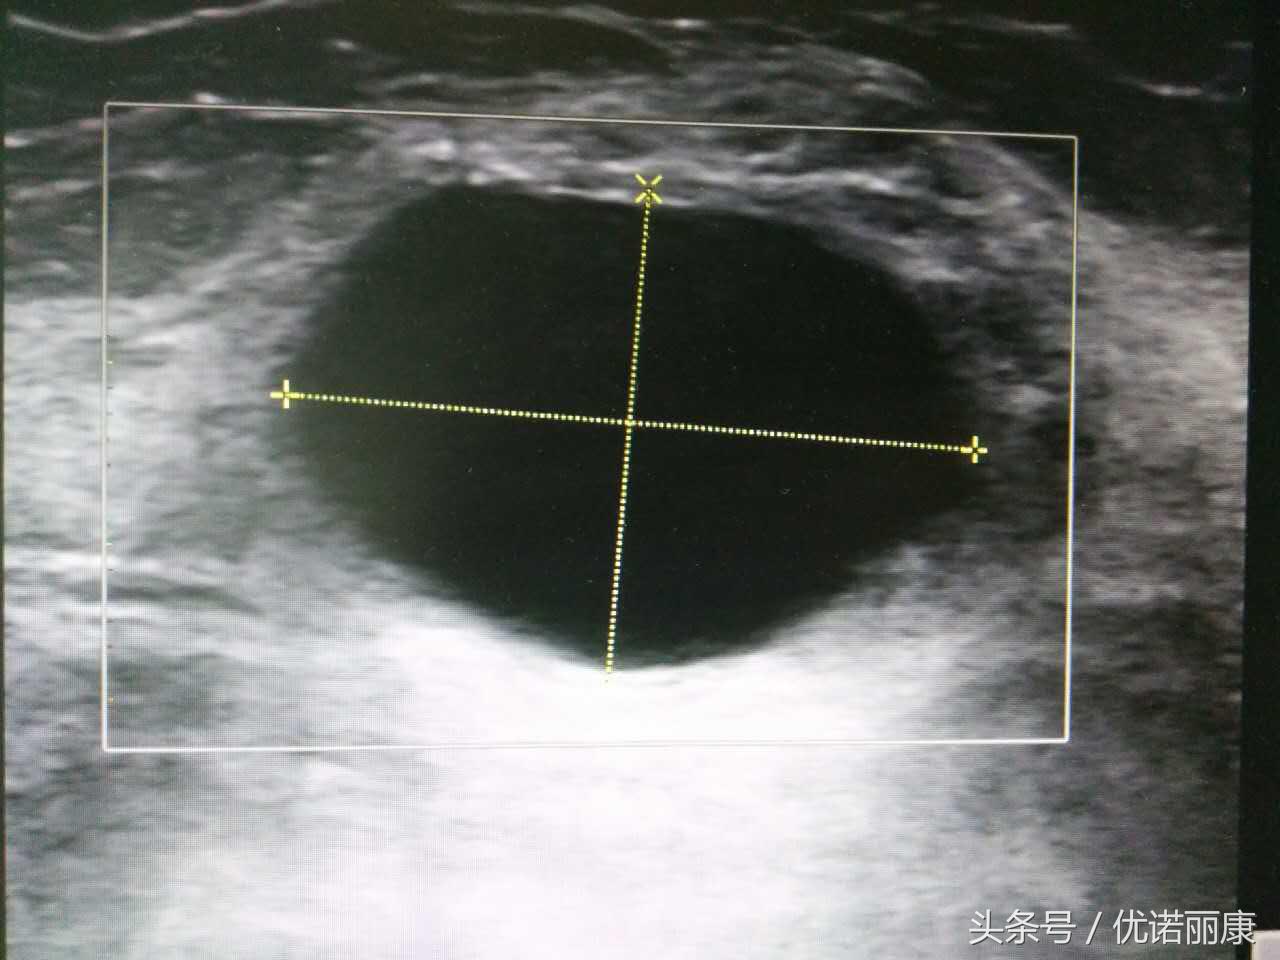

乳腺囊肿

肿块边缘光滑,内部液体回声均一